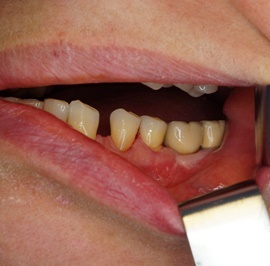

Pacjentka lat 58, prowadzi aktywne życie zawodowe. Odczuwała dyskomfort przy użytkowaniu protezy, dodatkowo przy uśmiechu odsłaniała klamry utrzymujące protezę.